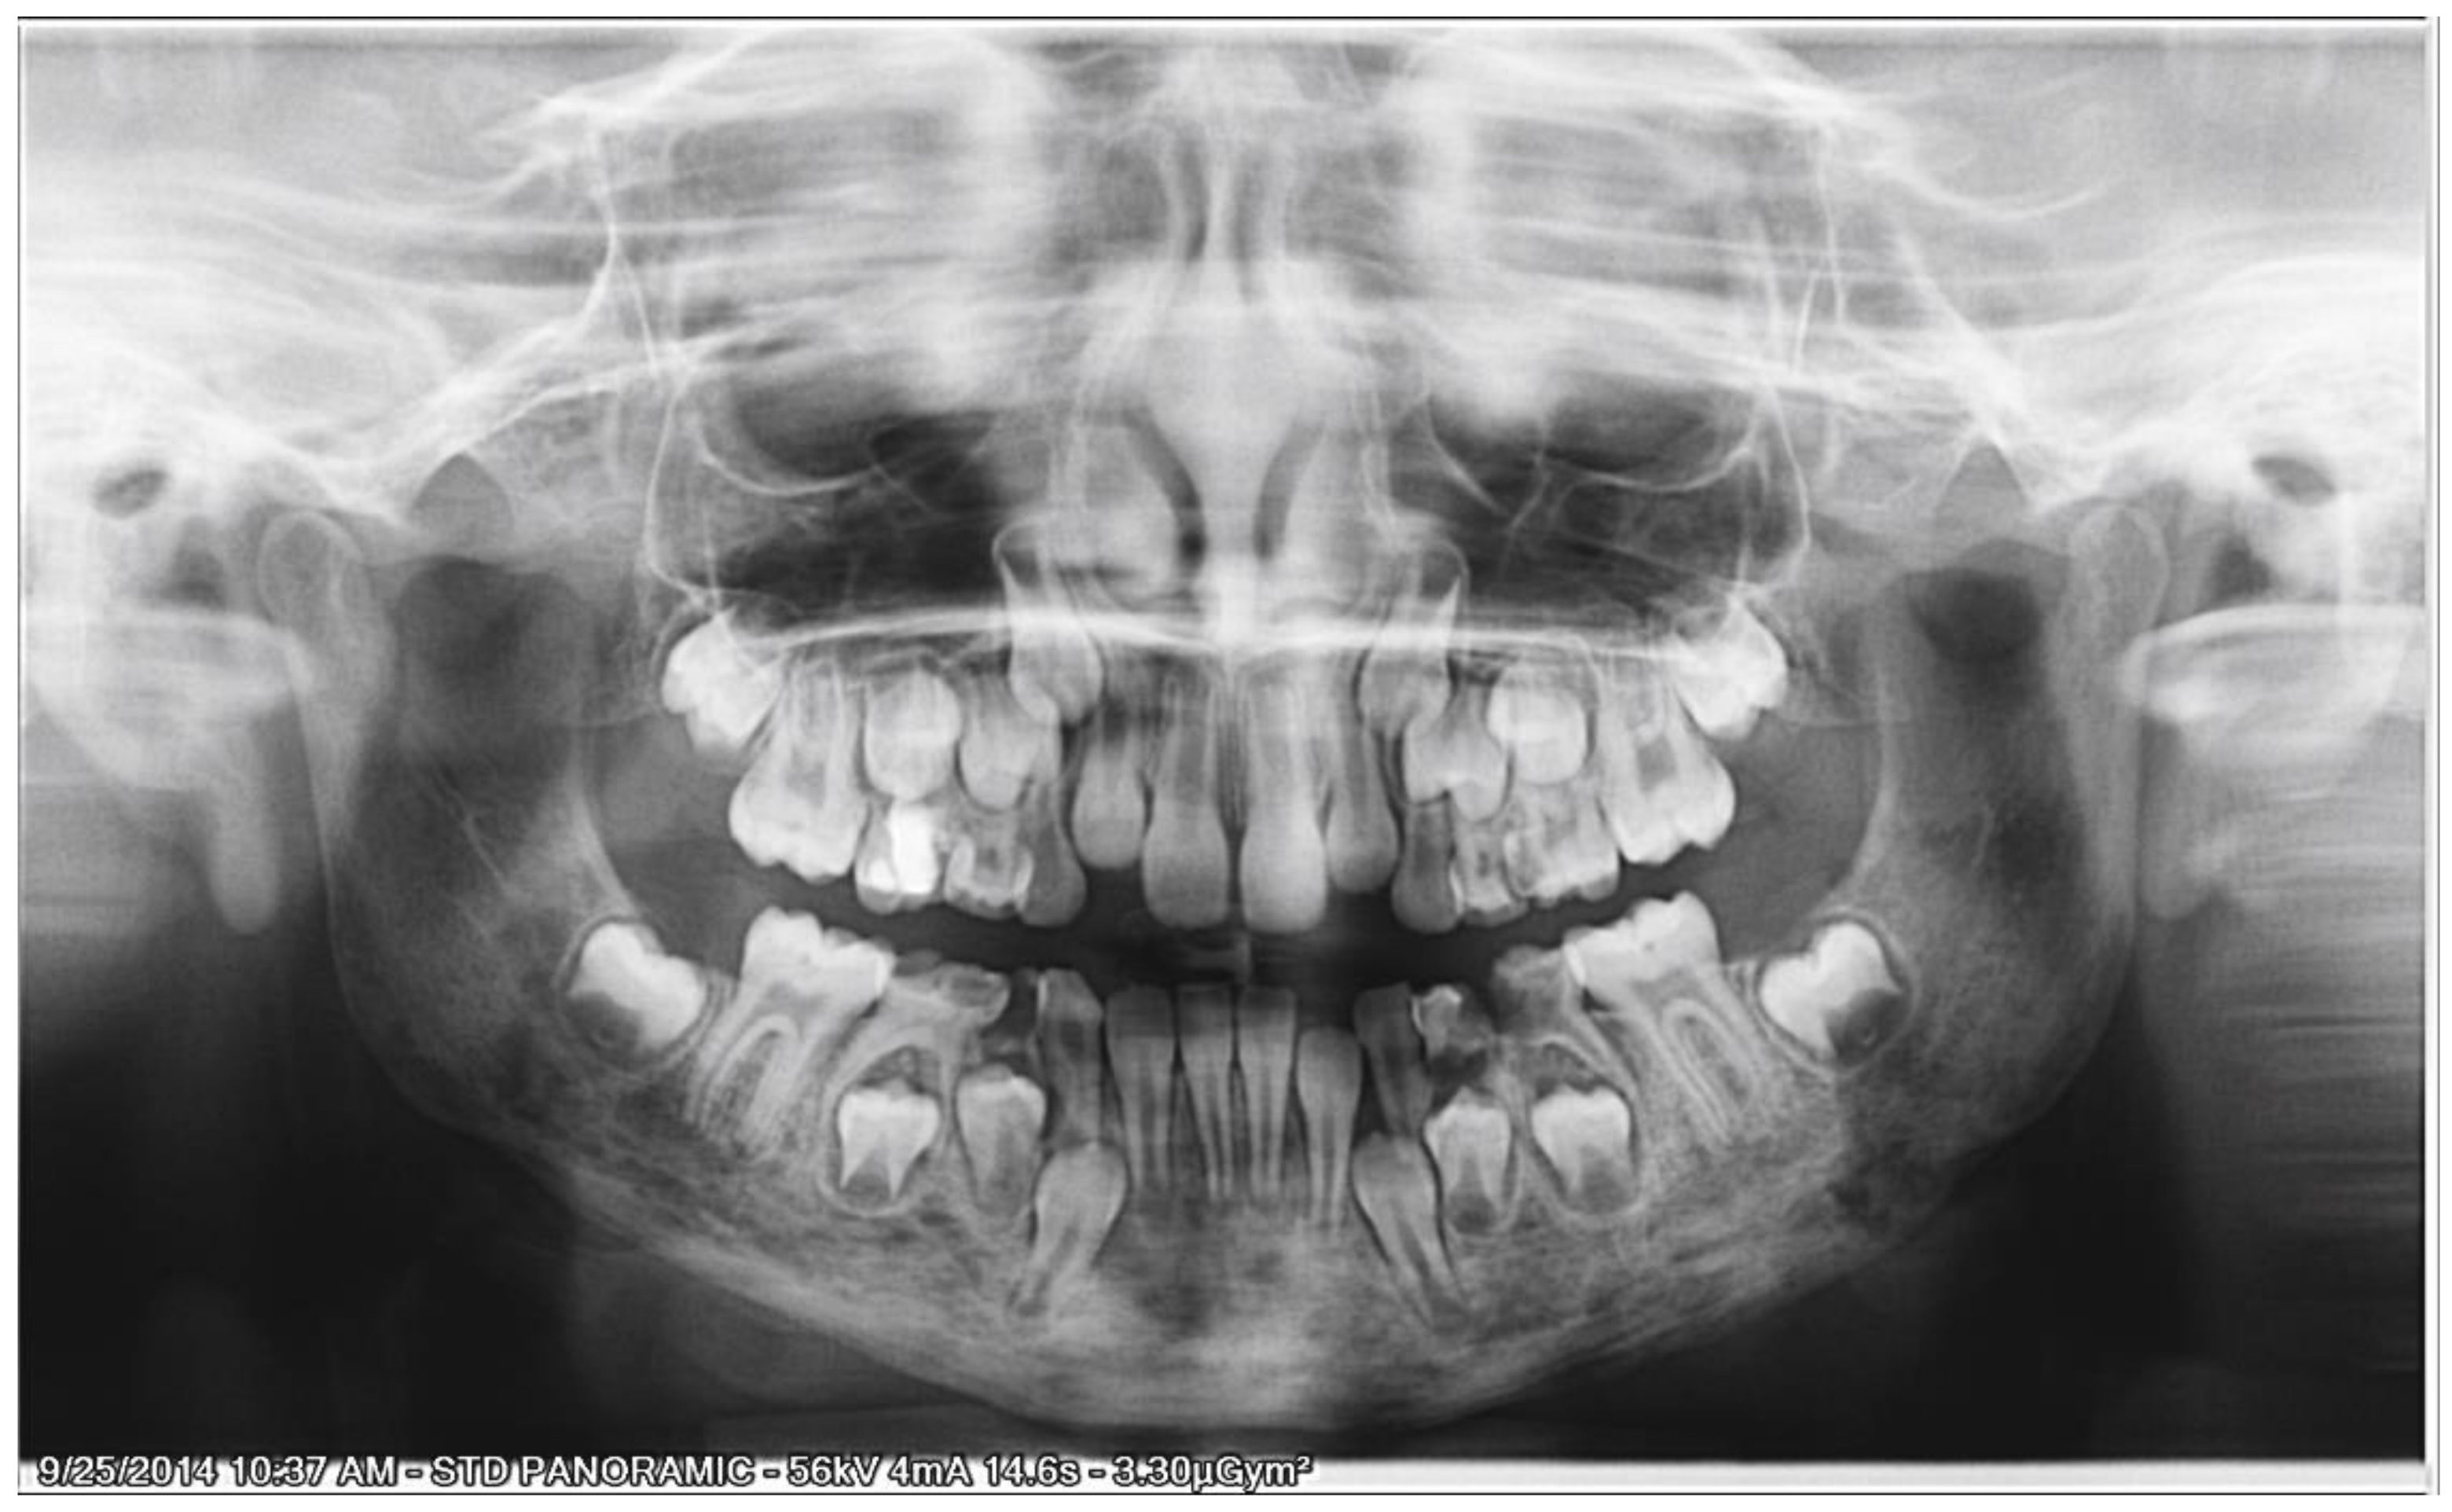

2.3.2. Second Phase of Treatment—2017—Bite-Blocks and Transpalatal Arch